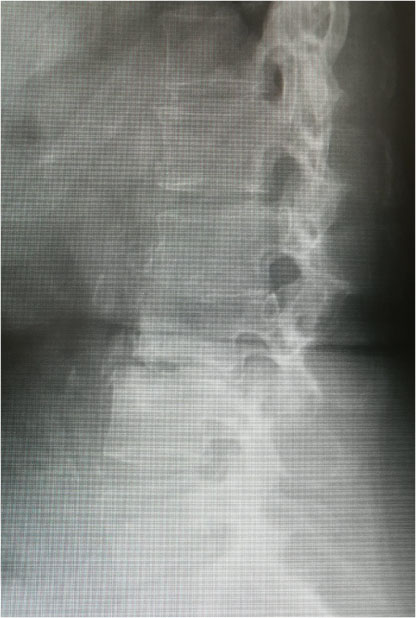

・本日の腰椎Xp:L2,3の椎体変形、癒合。L3下面、L4上面の骨硬化像。L2/3、L3/4椎間腔狭小化。